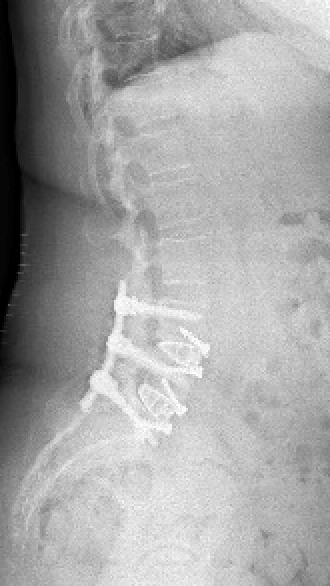

Colonne vertébrale lombaire / Rachis lombaire